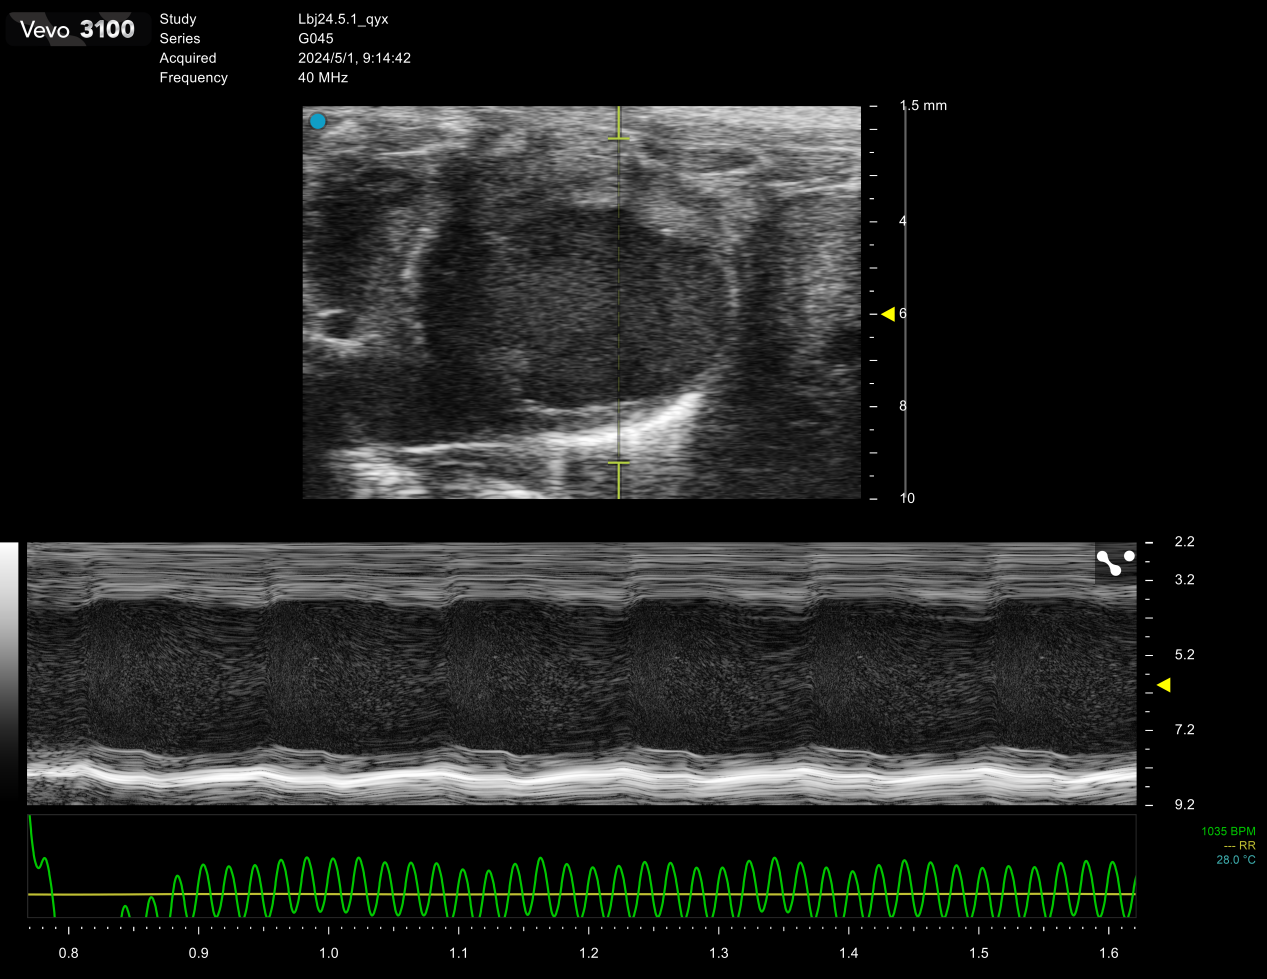

SiliconWave 60高频超声

1.心脏疾病常见的如心肌梗塞,心肌肥厚,心衰及高血压等。

2.血管疾病比如观测动脉粥样硬化斑块的形成与消融,血栓的形成与消融。

3.肿瘤动态监测肿瘤体积的研究可追踪肿瘤随时间的生长与转归。

4.肝脏疾病对脂肪肝、肝硬化、肝肿瘤等进行探测和定位,追踪病灶的进展。

5.胚胎发育可以实现从胚胎发育第五天开始到新生再到成年小鼠的发育研究,检测胎盘、脐带血流,分析小动物心脏发育相关重大遗传性疾病的发生、发展的规律及治疗方案等。